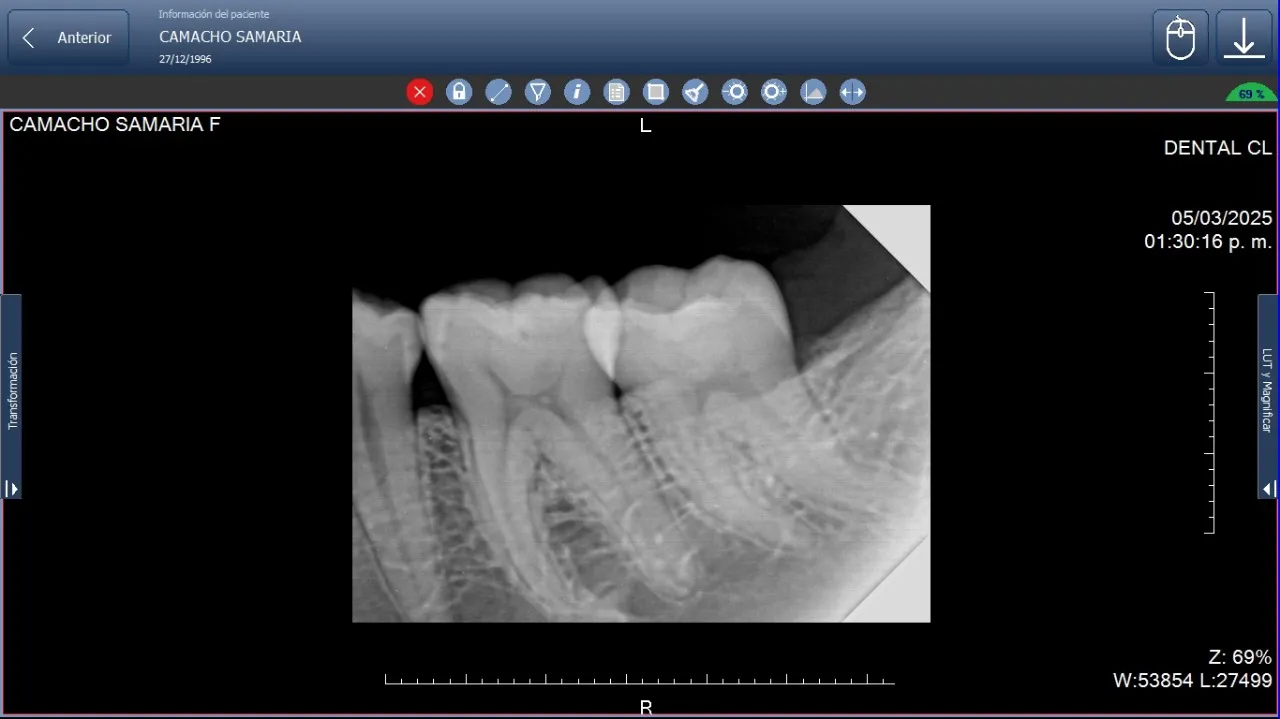

Imagen digital de radiografía periapical de dos muelas destacando las ventajas del rayos X digital frente al convencional en odontología.

• Comparación directa: En la evaluación clínica, la comparación entre imagen digital vs la placa de equipos tradicionales evidencia una nitidez superior en las imágenes digitales, lo que facilita la detección temprana de lesiones cariosas, fracturas radiculares y alteraciones periodontales.